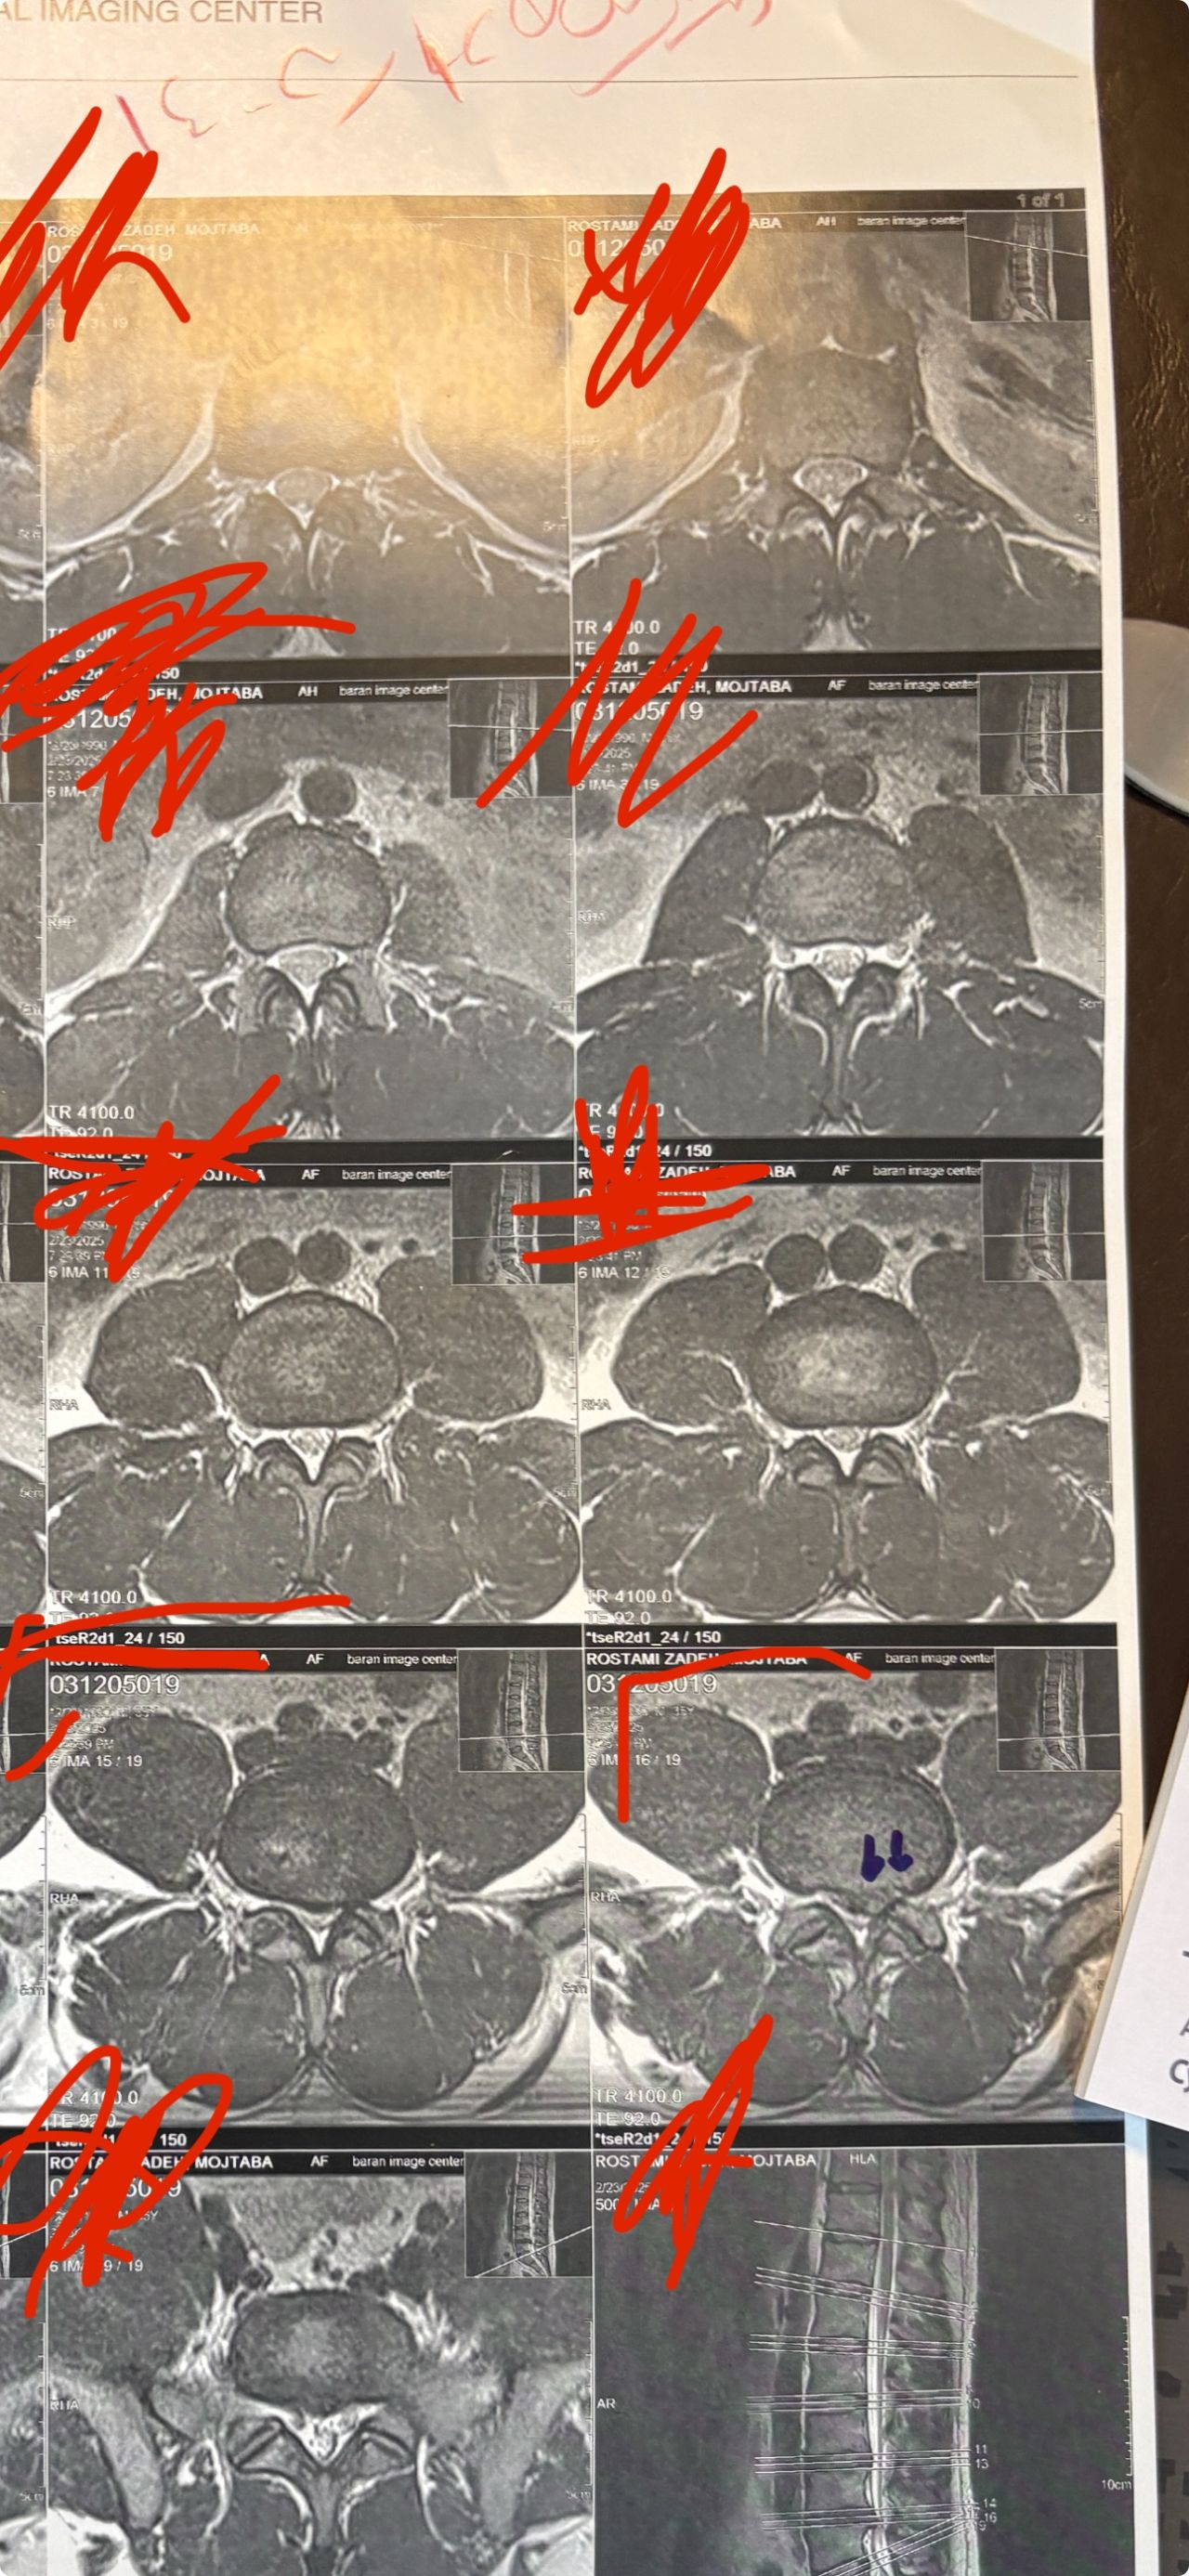

41 years old man presented to my clinic in October 2023 with acute and sever R neck pain with radicular pain to his R upper extremity along C6 dematom since 2 weeks ago. Examination didn’t show any upper motor signs. Was suggested urgent surgery

I ordered EMG/ NCV : showed mild R C6, C7 irritation without any active axonal loss

In his MRI was reported R. para R. IVF Massive extrusion. I decided to control his pain and manage this patient with reevaluation of patient every other session. For 5 sessions i just used acupuncture and laser and IFC and mild adjustments to his R. T3-T7 and mild arthosteem to above and below involved segment. Cervical adjustment considered contraindicated for this patient. From session 6th- 8th i started to use mild/gentle cervical decompression. He used soft cervical collar all the time. His pain decreased by 80 percent

I gave him cervical traction pump to be used 3-5 times per day at home for the next 3 months and i released the patient. He was evaluated every week once for one month and after that every 2 weeks. After 3 month I repeated MRI. Size of the herniated disc was reduced greater than 50 percent. Asked him to do another mri in 6 months

In general: Precise selection of the patients, examination,diagnosis, plan of management, reevaluation and treatment can be done by doctors of chiropractic for the patients with spinal disc herniation and stenosis Moreover giving reasonable time to these kind of patients under direct supervision by their chiropractic doctors can prevent unnecessary surgery. Proper selection of these kind of patients is another important fact that can be done precisely by chiropractors.

MRIs before and after proper management of this patient: